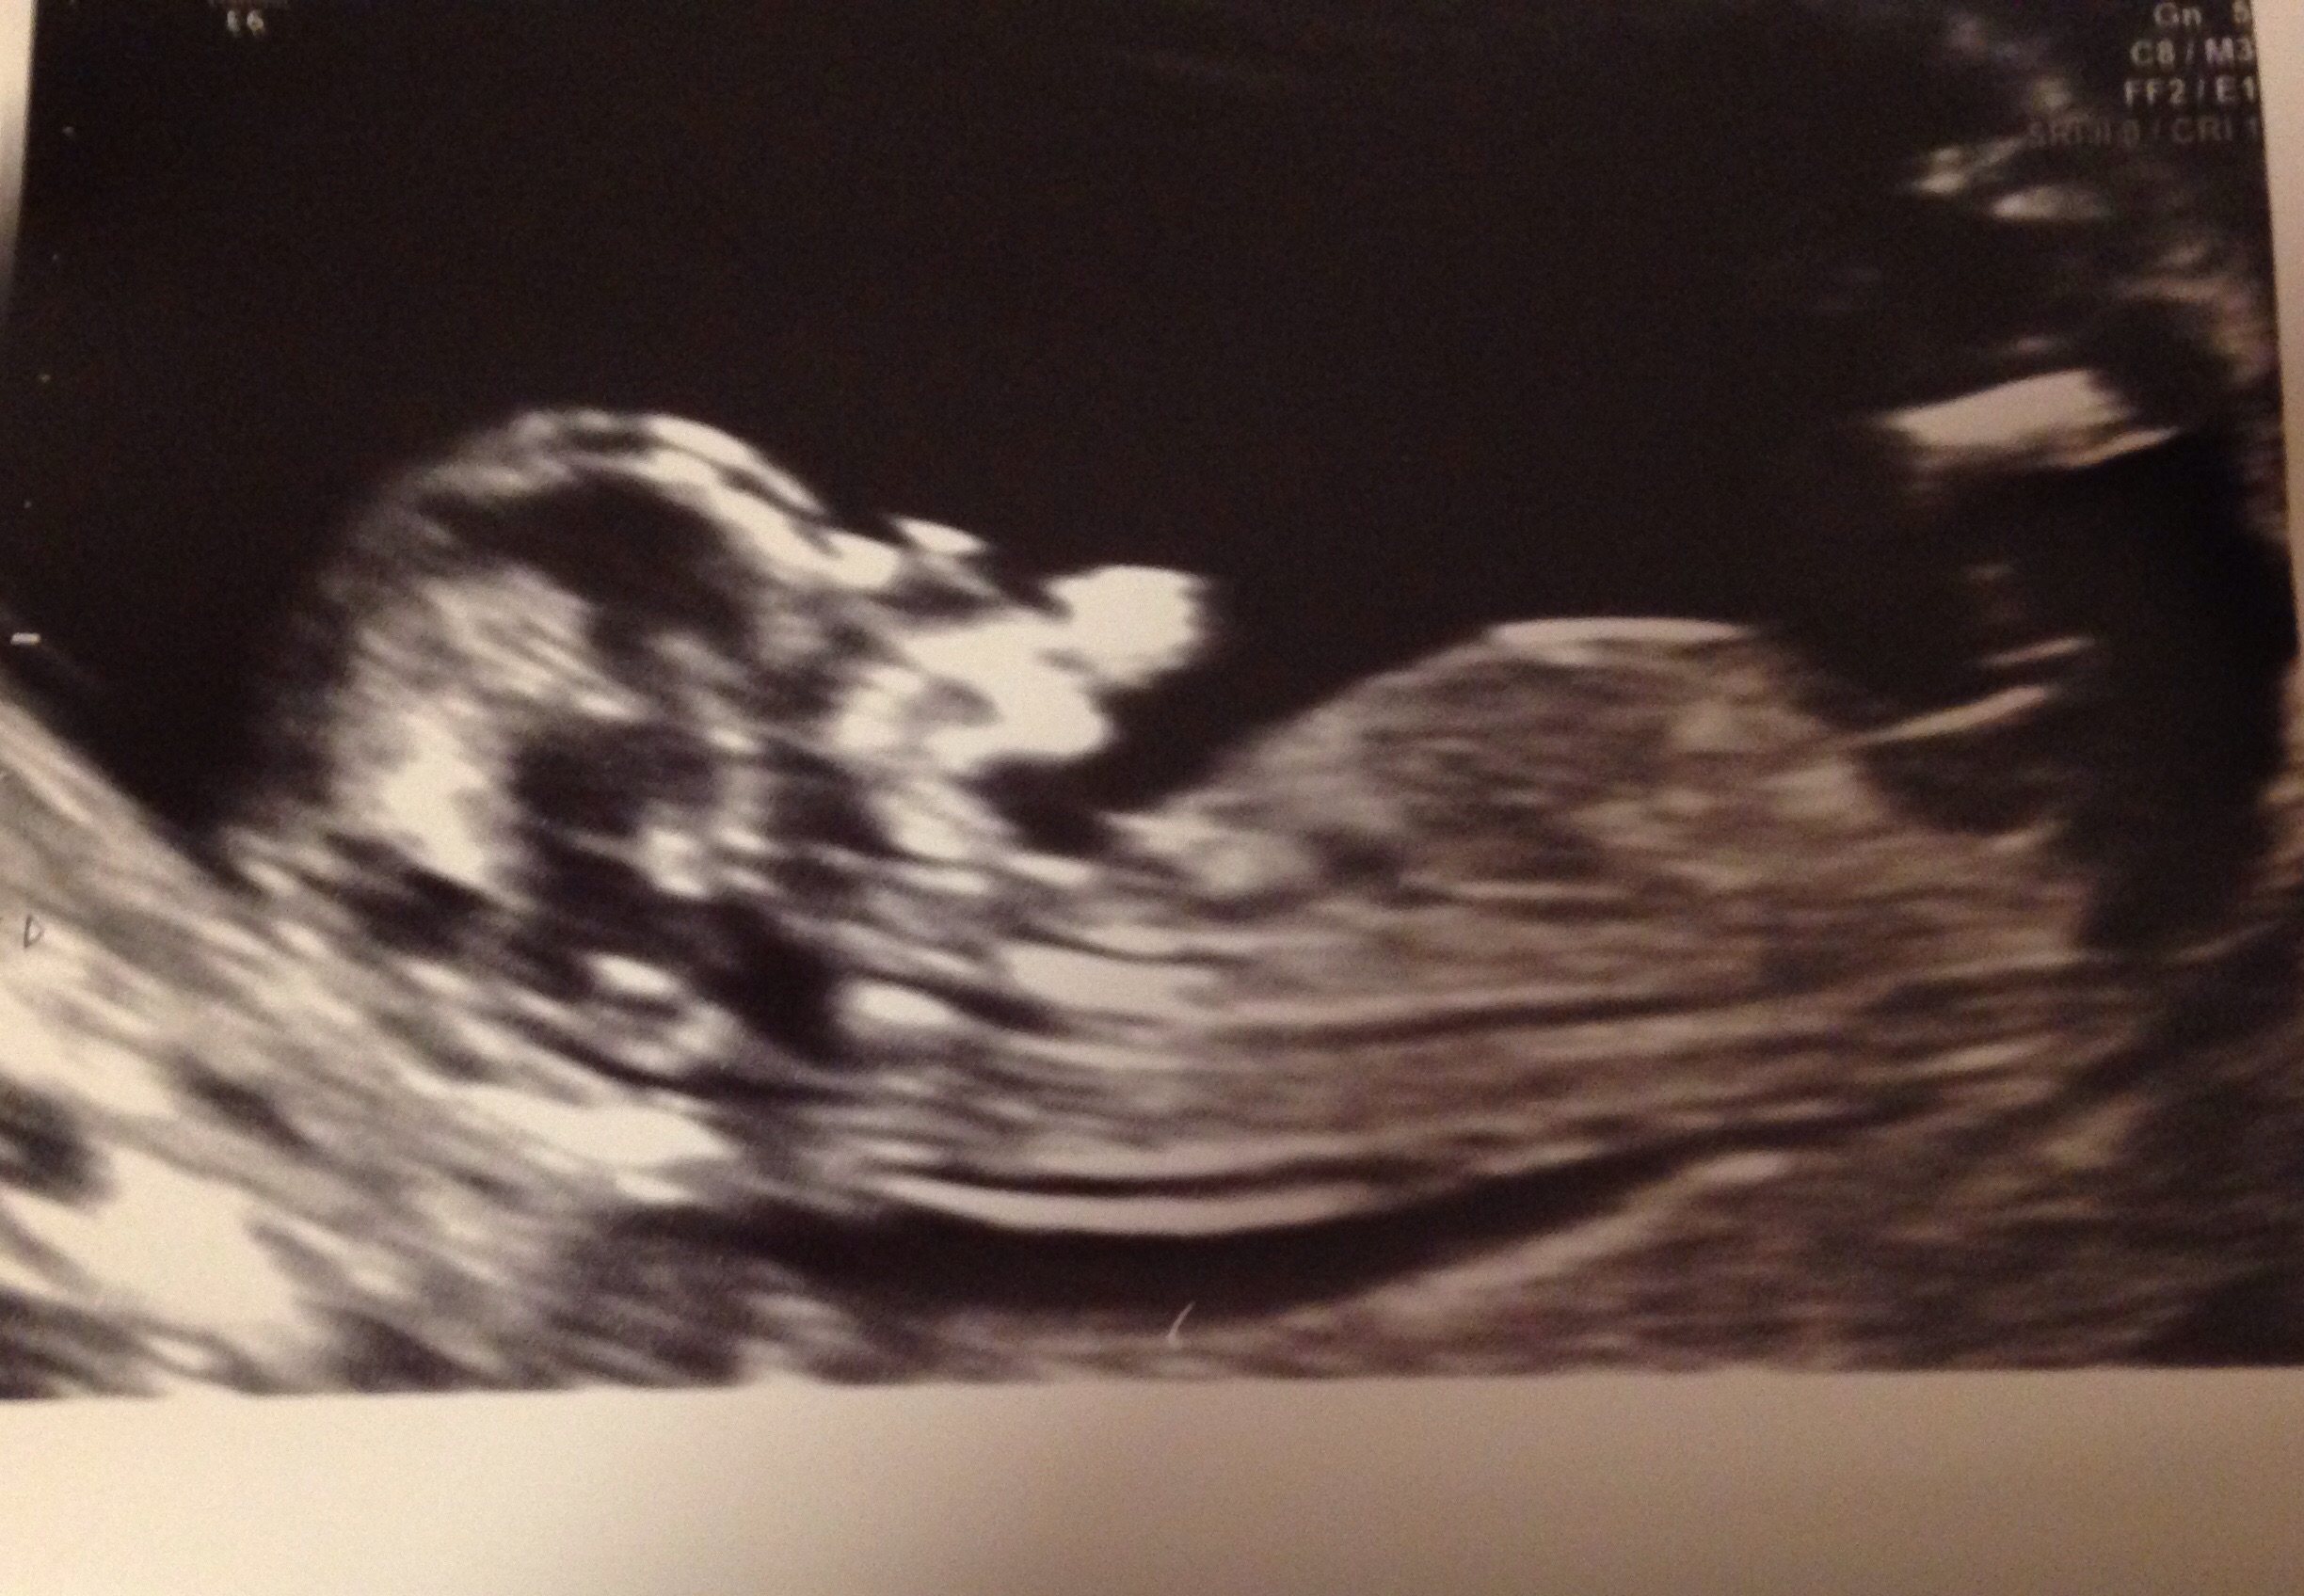

My friends first scan any nub Attachment 21315experts please ??

That's. Tricky one.. First glance I thought boy but zooming in looks like part of the nub is missing and looks girlie but less then 12 weeks isn't the best shot they say closer to 13 weeks is best x

Early but guessing boy :)

I'm thinking boy definitely

early for a guess, but looking blue

Leaning boy